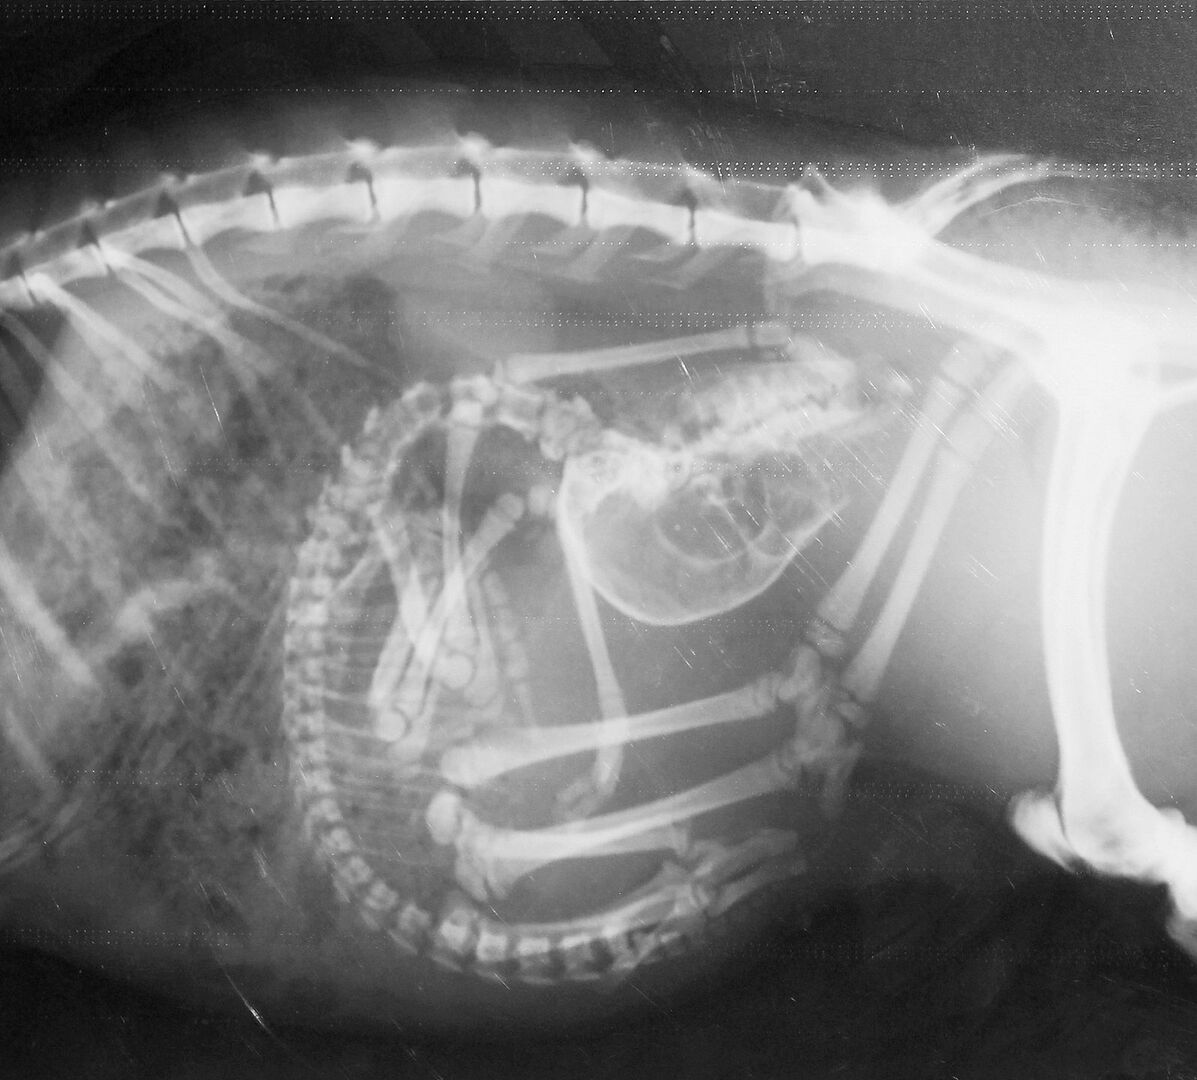

Erstaunlich, das Gerippe eines Seepferdchens! Wie ein Kunstwerk zeigen sich die Knochen, die der Bezeichnung Knochenfische alle Ehre machen. Wundersam wirkt das filigrane Schlangenskelett. Im Röntgenraum der Tierklinik im Basler Zoo wird rasch klar, wie komplex die Arbeit eines Zootierarztes ist. Er muss die Röntgenbilder zahlreicher verschiedener Arten interpretieren. Doch die Schwierigkeit beginnt schon vorher. Wie bekommt man Tiere, vom Seepferdchen bis zum Geparden, auf den Röntgentisch?

Dr. Christian Wenker ist froh über die Möglichkeit, Tiere röntgen zu können. Der leitende Veterinär im Basler Zoo erklärt: «Dank dem bildgebenden Verfahren haben wir in der Zootiermedizin ein rasches Resultat.» Bei Blut- und Kotuntersuchungen müsse bis am nächsten Tag gewartet werden. Schnelles Handeln ist in der Zootiermedizin wichtig. Zeigen Tiere Krankheitssymptome, liegt ein gravierendes Problem vor. Sie verbergen Unwohlsein, denn in der Natur werden schwächelnde Tiere durch Feinde eliminiert.